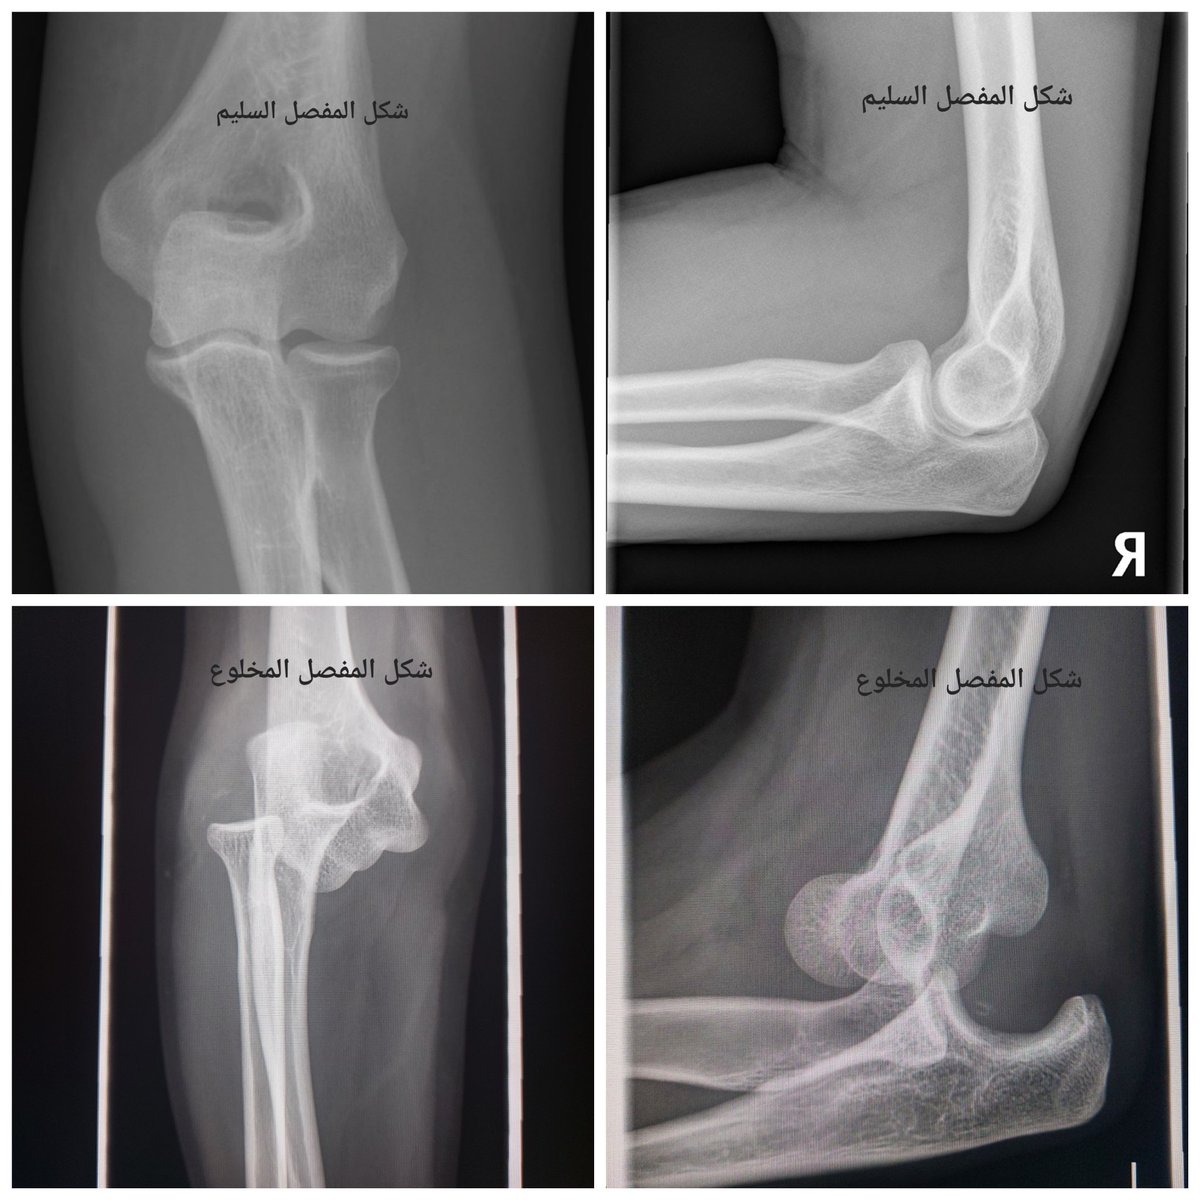

هنا استعرض حالة للاعب كرة قدم تعرض لخلع في مفصل المرفق

يتم غالبا اعادة المفصل الى مكانة في قسم الطوارئ و يتم وضع جبيرة مؤقته